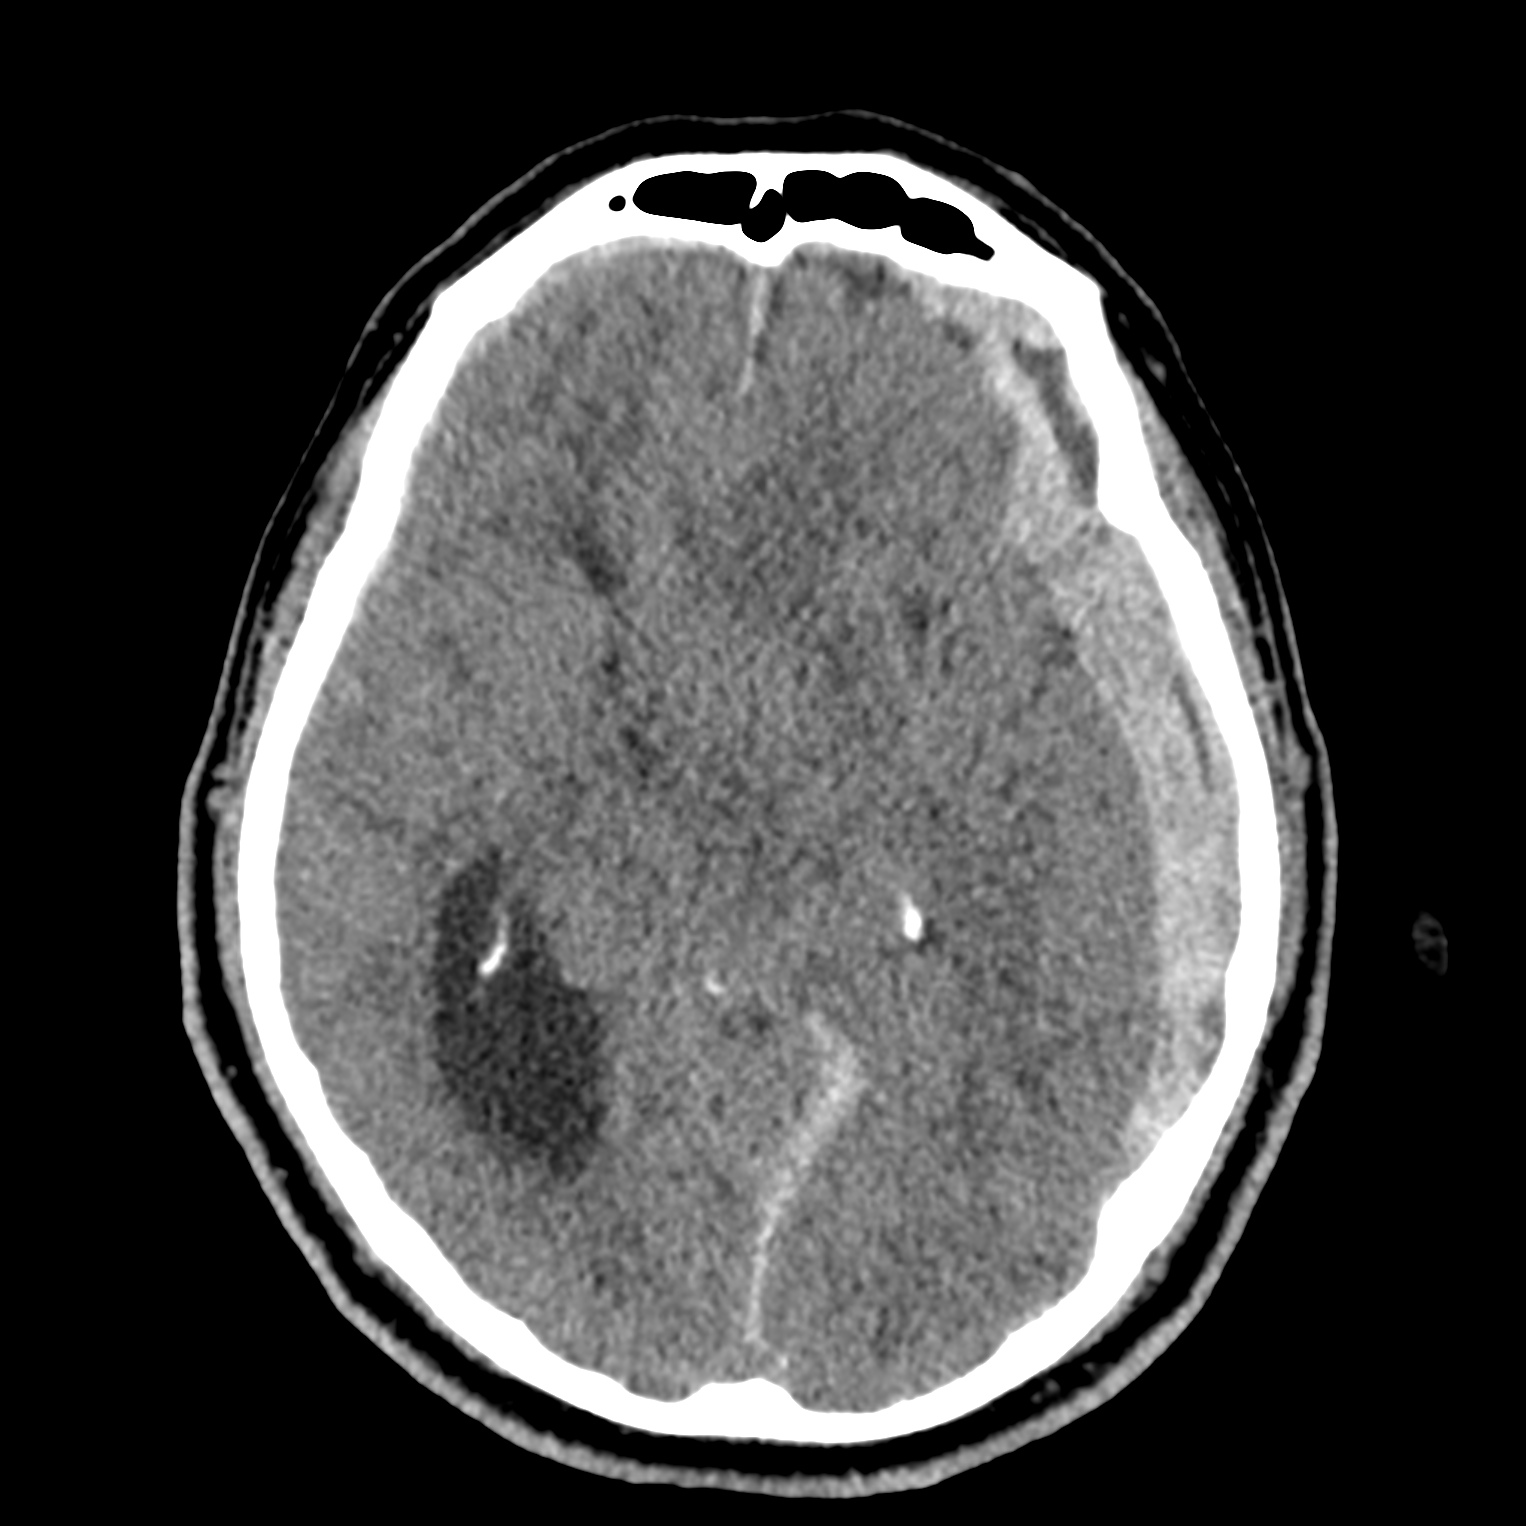

ちなみに画像診断とは、CTやMRIなどの画像を見て、正常か異常か、異常であればそれが何なのかを診断する仕事です。

Case courtesy of Andrew Dixon, Radiopaedia.org. From the case rID: 32383

医療従事者でなければ何のメリットも無いかもしれないのですが、実際の画像を自分でスクロールしながら学ぶことができるというのは、ものすごく大きなことだと思います。

さらに症例の解説を付け加えたら、読影能力アップのための強力なツールになるのではないかと期待しています。